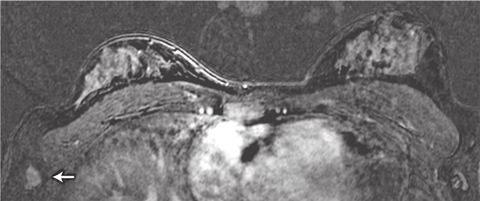

We identified two patients with lesions potentially putting them at higher risk of breast cancer and one with metastatic cancer in an axillary lymph node. The lymph node metastasis was not initially identified in the MRI scan: the patient palpated the node herself 1 month after imaging was done, and when the MRI scan was viewed retrospectively, the metastasis was in fact visible (Box 5). The patient’s imaging occurred early in the study, and failure to detect the cancer was the result of inexperience in interpreting breast MRI scans at that stage. This underlines the importance of carrying out breast MRI examination and reporting in centres that have expert multidisciplinary experience in breast surveillance, including MRI.